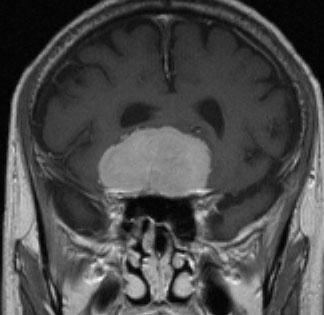

側脳室三角部髄膜腫 lateral ventricle (trigon) meningioma

50歳くらいの女性に偶然発見された三角部髄膜腫です。この部位はとても巨大にならないと症状が出ないので,しばらく様子を見ることにしました。

5年後です。増大傾向が止まりません。大きくなると手術リスクがすごく高くなるので,開頭手術で摘出することにしました。

右側は,手術翌日のMRIです。頭頂部の皮質経由で腫瘍は全摘出できています。専門的には,頭頂部経皮質到達法 parietal transcortical approach, high-parietal approachといいます。この患者さんは幸い頭頂葉症状は全く出ませんでした。でも巨大な三角部髄膜腫になると頭頂葉症候が手術後遺症として残ることがあります。でも慎重な手術をすれば日常生活に大きな支障となることはほとんどないでしょう。